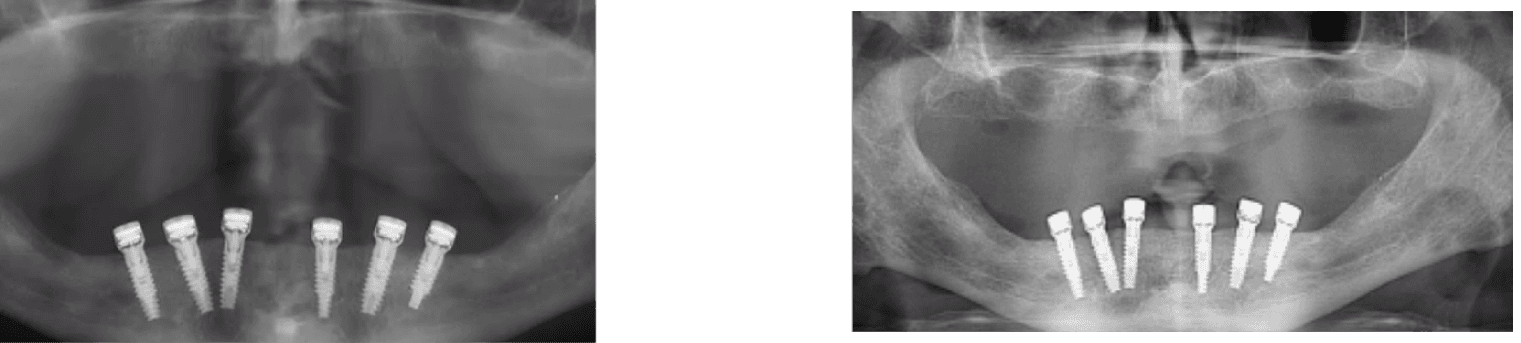

A 70-year-old heavy smoker presented with a fully edentulous mandible and clinically poor bone quality. Six implants were placed, each fitted with a MED healing abutment to enhance bone regeneration and support early osseointegration. Despite the compromised bone condition and smoking-related healing challenges, the patient demonstrated an excellent biological response throughout the recovery phase.

After only 45 days, radiographic assessment confirmed successful osseointegration across all six implants, allowing for full-arch prosthetic restoration. The patient received a stable mandibular bridge within a significantly shortened treatment period. The use of MED healing abutments contributed to rapid bone maturation, improved implant stability, and an accelerated rehabilitation process even in a high-risk, heavy-smoking patient.

A 73-year-old female patient with long-standing type II diabetes mellitus (average glucose level ≈ 200 mg/dL) presented with edentulism of the lower jaw and poor bone quality, classified as D4 bone - characterized by thin cortical plates and sparse trabecular bone. Seven implants were placed immediately after extractions, each equipped with a MED healing abutment to enhance bone metabolism and accelerate osseointegration, addressing the impaired healing potential typically associated with diabetic conditions.

Despite the compromised systemic condition and low bone density, the healing process was remarkably successful. Within less than three months, complete osseointegration was achieved across all seven implants, enabling delivery of the final prosthetic restoration. The use of MED healing abutments significantly improved local bone response, stabilized the peri-implant tissues, and facilitated rapid and predictable rehabilitation in a high-risk diabetic patient with D4 bone quality.